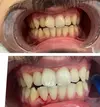

Zirconium applications

Porcelain applications

Laminate veneer